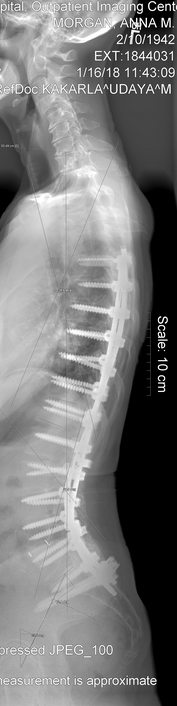

I go January 16 to have my year X-ray and be checked. If everything is healing correctly and the hardware is holding, I will accept this as my new normal.

My year is up and I have had my 1 year x-rays and Surgeon appointment. Everything looks to be holding. I guess you would say that I no longer have scoliosis. I do still have that cardboard feeling in the muscles of my back. I mentioned to Dr. Kakarla that when I try to lift a gallon of milk the back goes into spasms and gets tighter. He decided that I needed another 30 sessions at physical therapy to make my upper body and legs stronger.

I still am doing the 4 mile hike. So with 3 times a week at PT and the hike my days are busy. Hope we can get started with our summer by Easter. Here are two views of my spine at my one year checkup.